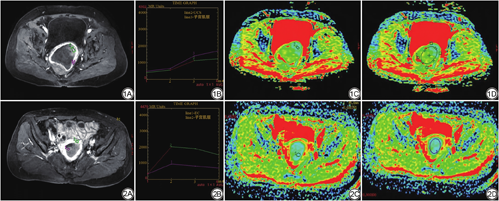

UCS组的TIC曲线类型中有20例为Ⅰ型流入型曲线(71.43%),3例为Ⅱ型廓清型曲线(10.71%),5例为Ⅲ型平台型曲线(17.86%),而EC组中有2例为Ⅰ型(4.08%),29例为Ⅱ型(59.18%),18例为Ⅲ型(36.74%)。两组TIC曲线类型差异具有统计学意义(χ2=40.484,P<0.01,表2)。两两比较提示,Ⅰ型在UCS中的所占比例高于EC,差异具有统计学意义(P<0.05)。Ⅱ型在EC中所占比例高于UCS,差异具有统计学意义(P<0.05)。Ⅲ型既可见于UCS亦可见于EC,差异不具有统计学意义(P>0.05)。相关图片见图1、2。

将DCE图像导入工作站,应用Functool软件处理其数据,于病灶最大层面增强最显著的实性部位放置ROI,同样避开囊变、出血及血管,获得病灶TIC。以病变强化第二期信号强度为基准,对病灶TIC类型进行分类,标准如下:Ⅰ型(流入型):较第二期强化信号,强化末期TIC上升幅度大于10%;Ⅱ型(廓清型):强化末期TIC下降幅度大于10%;Ⅲ型(平台型):TIC变化幅度介于10%以内[10]。本研究所有ROI均由两名有阅片经验的影像诊断医师共同勾画获取,如出现争议,由科室主任医师评估结果并作出一致决定。

本研究结合动态增强MRI,采用TIC进行定性分析以便更加直观、便捷地反映病灶性质。研究结果表明UCS组TIC多为Ⅰ型和Ⅲ型,而EC的TIC类型与陈苑等[12]研究结果较为相似多呈Ⅱ型和Ⅲ型,两组TIC类型差异具有统计学意义。Ⅰ型在UCS组中占比最高,即UCS强化方式为持续强化;EC组多表现为Ⅱ型,即该组强化方式为早期快速上升,达到峰值后缓慢下降。UCS中肉瘤成分分化程度低,富含大量新生血管,血供丰富,强化明显[17, 18];而EC为单一癌性成分,且EC是一种乏血管性肿瘤,其强化程度相对较低[19, 20]。此外,EC的癌细胞可浸润破坏正常血管,诱导产生动-静脉瘘及畸变小血管,致病灶内微血管灌注率低,从而出现中度强化、晚期不强化的强化方式[21]。